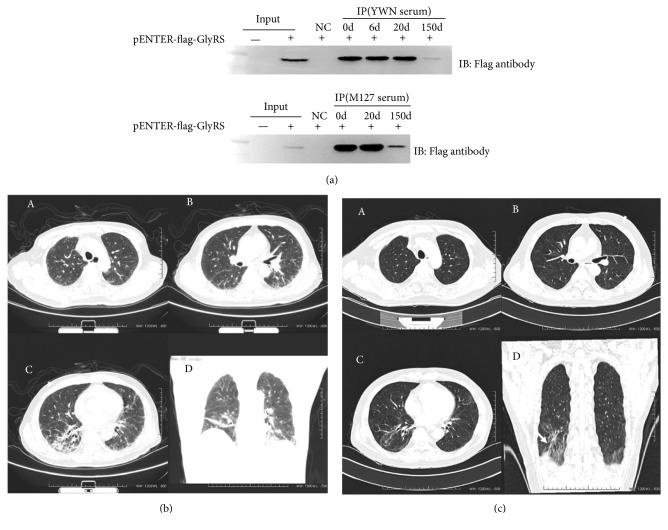

Sera of 236 Chinese patients with myositis were screened for anti-EJ by a novel immunoprecipitation assay of flag-tagged GlyRS. Anti-EJ positive patients are evaluated for the clinical features and cytokine profile.

The sera from 4 of 236 adult myositis patients were found to carry the anti-EJ using established novel immunoprecipitation assay and immunoblotting. The prevalence of anti-EJ in our cohorts is about 1.7%. The decline of anti-EJ level was detected in two patients during disease remission. Interstitial lung disease and muscle weakness, but not skin involvement, are common clinical features of anti-EJ positive patients. Moreover, using a cytokine profile analyses, we found that the serum levels of IP-10, IL-6, MCP-1, and VEGF were significantly elevated in patients with anti-EJ and gradually decreased during disease remission of two patients, whereas IL-8 level was obviously reduced in these patients.